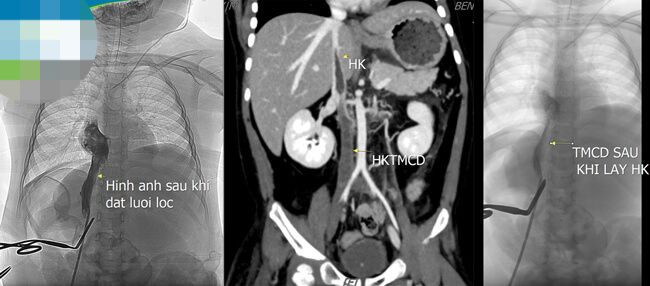

| Hình ảnh huyết khối của trẻ trước và sau khi được phẫu thuật. |

Tiếp nhận ca bệnh, Thạc sĩ, bác sĩ chuyên khoa II Lê Đình Công, Trưởng Đơn vị Điện quang can thiệp, Phó Trưởng khoa Chẩn đoán hình ảnh cho hay, ngay từ khi hội chẩn, mục tiêu của ê-kíp là tiếp cận tĩnh mạch chủ dưới đoạn sau gan và trên thận, khơi thông dòng chảy tĩnh mạch chủ dưới, sau đó, đặt lưới lọc để tránh huyết khối trôi về tim gây thuyên tắc phổi.

"Rất may mắn, cuộc phẫu thuật diễn ra thành công. Đánh giá siêu âm sau 8 giờ, trẻ tái thông dòng chảy tĩnh mạch thận 2 bên, tái thông tĩnh mạch chủ dưới đoạn sau gan và ngang tĩnh mạch thận, không có bằng chứng huyết khối trôi về tĩnh mạch phổi 2 bên”, bác sĩ Công chia sẻ.